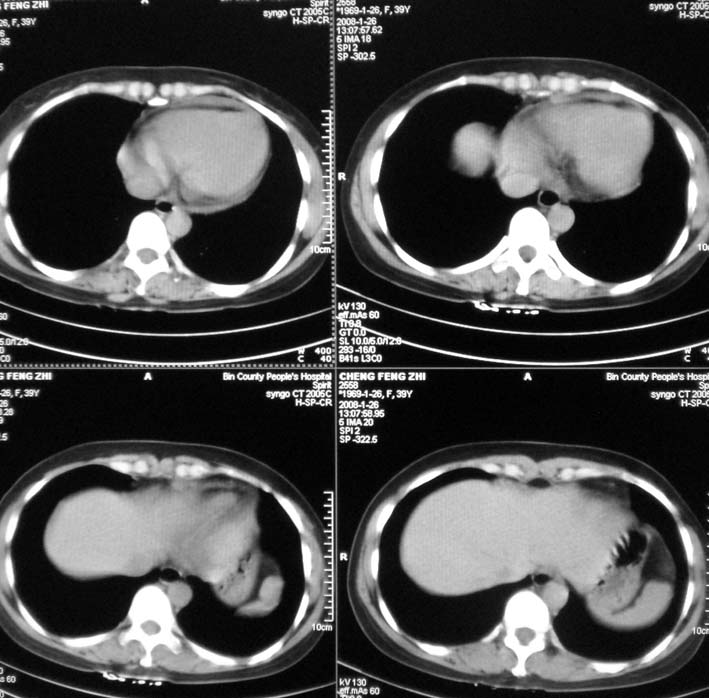

以下是引用guoke在2008-1-27 14:15:00的发言:[br]纵隔增宽,纵隔内血管境界不清,心包积液,考虑纵隔淋巴瘤.[br]

以下是引用随光逐影在2008-1-27 15:52:00的发言:[br]1)考虑为:淋巴瘤。建议:行进一步检查。2)心包积液。